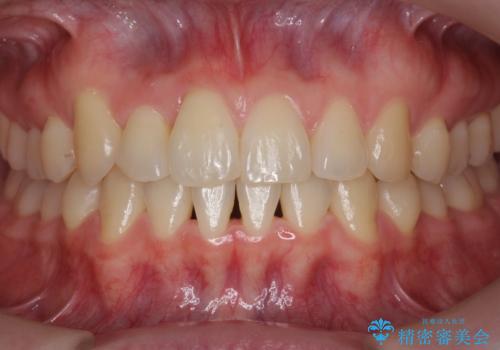

引っ込んだ前歯を並べる 歯を抜かないマウスピース矯正

- 右上の前歯が内側に入っているのを気にして来院。

右上の奥歯を後ろに移動して、前に出すスペースを確保してから並べました。

奥歯を後ろに送るために、矯正用インプラントを使用しています。

前歯が内側に入っていると、笑った時にそこが黒くなり、歯が抜けたように見えます。

口を開けたとき、笑顔の印象が大きく変わり、大変喜んでいただけました。